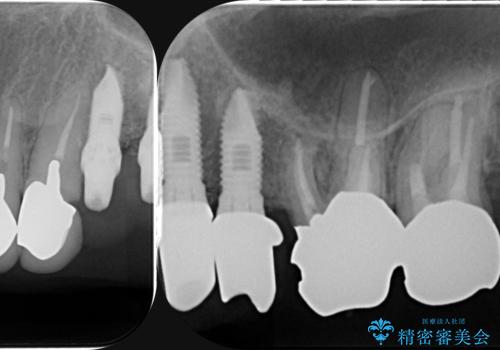

虫歯による歯の喪失 インプラントによる咬合機能回復

- 深い虫歯や歯の破折、多数の問題を口腔内に抱えて来院されました。

虫歯の徹底的な除去、安定した噛み合わせを達成するインプラント治療、深い虫歯、根管治療といった複数の治療項目を一つづつ積み重ね、長期的な予後を目指します。